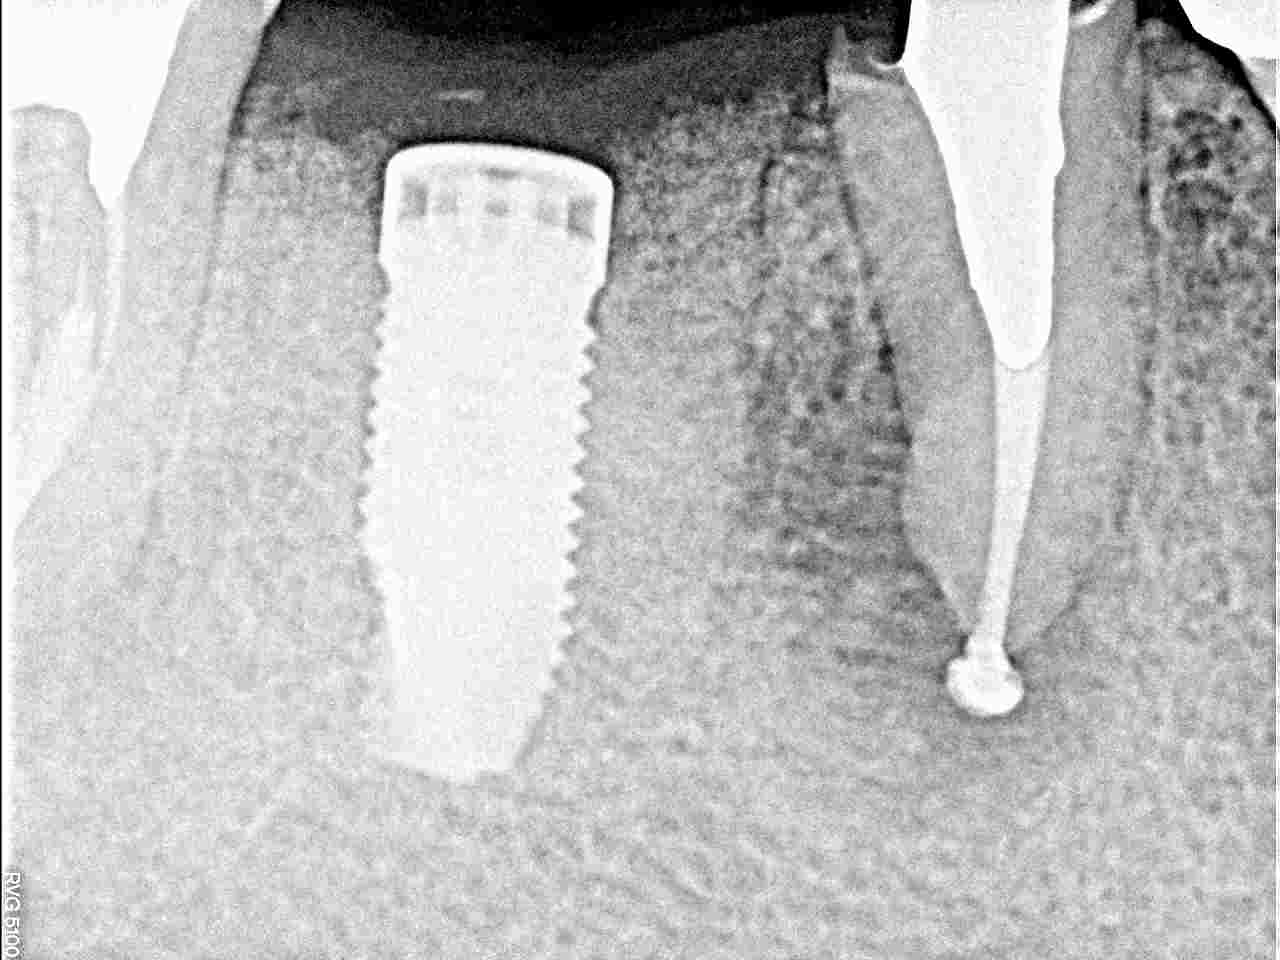

このように埋入しています5mmの13mmというインプラントサイズになります

実をいうと手前の根尖病巣がインプラント埋入より治らなくて厄介でした

仮歯に置いているのですが、根尖病巣が引かないため外科処置を行っています